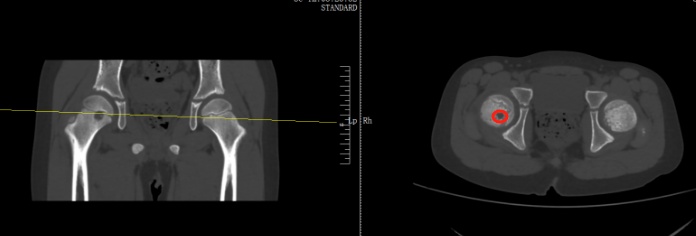

当地医生诊断为右股骨近端占位,怀疑内部可能长了肿瘤。扬扬妈妈听到医生的话心里直害怕,夫妻两人又马不停蹄带孩子来到了骨科医院进一步检查,扬扬被确诊为右股骨近端肿瘤。

好在从影像上来看,初步考虑是偏良性。在跟家长商讨过后,医生为扬扬执行了前侧入路右侧股骨头钻取刮除、取自体髂骨骨移植术,手术顺利切除病灶,并补上了股骨的“漏洞”。